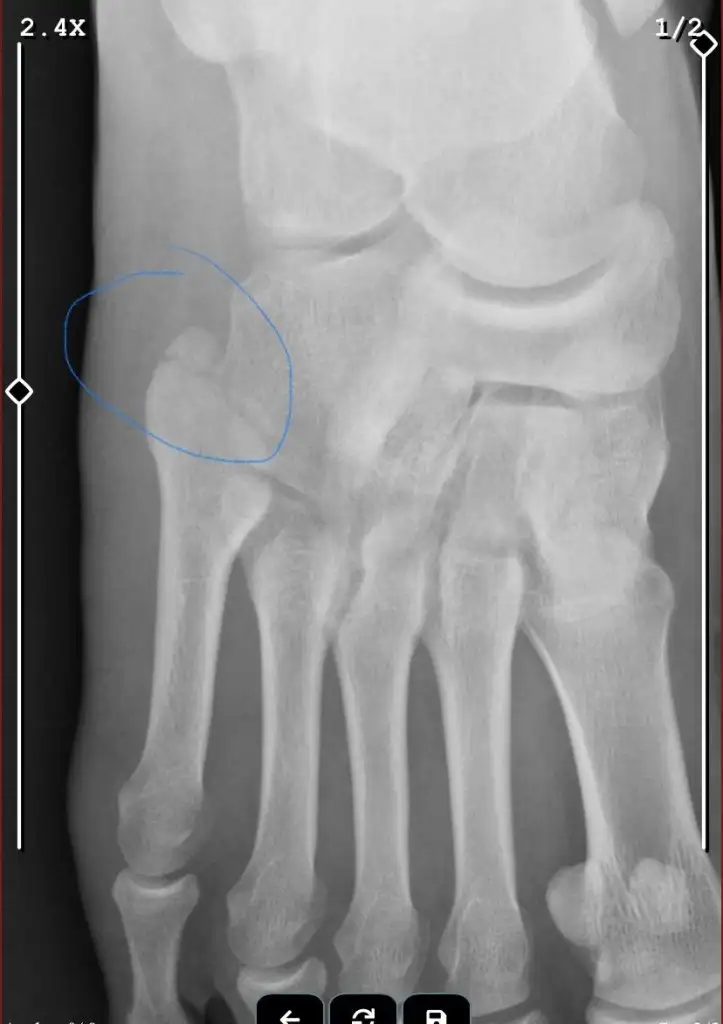

Selamlar herkese, geçen günlerde ayağım'a darbe aldığım için şişti ve morardı acile gittiğimde röntgen çektiler ve çatlak olduğunu söylediler sonra ortopedi doktoruna yönlendirdiler. Ortopedi doktoru röntgene bakarak kırık değil yumşak doku zedelenmesi alçıya alacağız en az 20 gün kalacak dedi. Acildeki doktorun dediği kafamı karıştırdı ve röntgen de çatlak olduğunu düşündüğüm bir yer var. Aşağıya röntgeni ekliyorum sizce çatlak mı?

Ortopedi doktorunu onaylıyorum. Çatlak veya kırık yok. İşaretlediğin alan anatomik olarak böyle parçalıdır.

Bir ayrılma görüyorum ama ayağın orijinal hali öyle mi bilmiyorum.Siz bence ikinci bir doktora gösterin.Kardesime yumuşak doku ezilmesi dediler kız sabaha kadar agladi sabah tekrardan hastaneye gittik meğer kırıkmış.